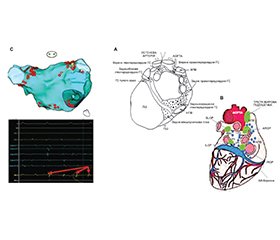

У багатьох пацієнтів з анамнезом пароксизмальної форми ФП, вторинної щодо ураження ВНС, ми зазвичай визначаємо два різних клінічних сценарії: адренергічну ФП і вагусну ФП [2]. Адренергічна форма ФП найчастіше виникає протягом дня, з денними епізодами, і провокується психофізичним стресом і фізичною активністю. Інколи такі самі ознаки можна спостерігати в пацієнтів з гіпертиреозом і феохромоцитомою. Вагусна ФП найчастіше вражає чоловіків і молодих (вік 30–50 років) пацієнтів без структурних захворювань серця. Вона частіше трапляється в пацієнтів з брадикардією, з нападами під час нічного відпочинку або відпочинку після вживання їжі; вважається, що провокуючими факторами є великі порції їжі, особливо ввечері, а також зловживання алкоголем. Крім того, у пацієнтів з адренергічною ФП значно частіше виявляють структурні ураження серця, ніж при вагусно-опосередкованих формах ФП. Однак ця клінічна диференціація, хоч і занадто жорстка і схематична, знаходить раціональне пояснення в анатомічних, патофізіологічних (рис. 1), а також біомолекулярних механізмах, що лежать в основі ролі ВНС у виникненні й збереженні ФП [4]. Фактично фокальний механізм ФП зумовлений:

1) симпатичним внеском у виникнення ФП через автоматизм (завдяки зменшенню вхідного калієвого струму і збільшенню струму, що активується гіперполяризацією під час діастолічної деполяризації) ранніх передсердних генеруючих деполяризацій (які впливають на 2-гу фазу потенціалу дії передсердь) і пізніх передсердних індукуючих деполяризацій унаслідок перевантаження кальцієм та аномального вивільнення кальцію саркоплазматичним ретикулумом;

2) адренергічним і вагусним внесками (червоні лінії та стрілки) за допомогою активації G-білків, регульованих калієвими каналами вхідного випрямлення (GIRK); і нарешті,

3) парасимпатичним внеском у механізми re-entry.

Відмінні анатомічні знання (рис. 3А) є обов’язковою умовою для кращого розуміння патофізіологічних механізмів і причин вибору на додаток до класичної ізоляції легеневих вен (ЛВ), абляційної стратегії, спрямованої на виконання абляції гангліонарних сплетень (ГС) на рівні анатомічних ділянок, де розташовані найважливіші ГС. Armour et al. [13] показали, що внутрішні передсердно-серцеві ганглії людини та пов’язані з ними нерви, розташовані в епікардіальній жировій тканині, утворюють п’ять ГС: 1) верхнє правопередсердне ГС (розташоване на задній верхній поверхні правого передсердя (ПП) поруч із місцем з’єднання верхньої порожнистої вени (ВПВ) і ПП), 2) верхнє лівопередсердне ГС (ганглії, що розташовані на задній поверхні лівого передсердя (ЛП) між легеневими венами (ЛВ)), 3) заднє правопередсердне ГС (на задній поверхні ЛП, що прилягає до міжпередсердної борозни), 4) задньосерединне лівопередсердне ГС (на задньосерединній поверхні ЛП) і 5) задньобокове лівопередсердне ГС (на задньобоковій поверхні основи лівого передсердя з передсердного боку від АВ-борозни). Окремі нейрони і невеликі ганглії також були розкиданими по тканинах передсердь і шлуночків (рис. 3А). Згодом Aksu and Pauza et al. [14] описали п’ять передсердних епікардіальних гангліонарних підсплетень (ГпС), що перебувають під нейронним контролем одного внутрішнього епікардіального ГС: 1) вентральне (переднє) правопередсердне ГпС, яке займає вентральну верхню частину правого передсердя, вентральний бік кореня верхньої порожнистої вени (ВПВ) і вентральну нижню частину правого передсердя; 2) вентральне (переднє) лівопередсердне ГпС, яке займає вентральну верхню частину лівого передсердя; 3) ліве дорсальне (заднє) ГпС, яке займає ділянку дорсальної лівої вінцевої борозни і середню частину лівого передсердя; 4) середнє дорсальне (заднє) ГпС, яке займає дорсальну верхню частину лівого передсердя та навколо серцевого м’яза; і 5) дорсальне (заднє) правопередсердне ГпС, яке займає дорсальну верхню частину правого передсердя, дорсальний бік кореня ВПВ і ділянку над міжпередсердною перегородкою. Цікаво також відзначити, що постгангліонарні нерви з вентрального правопередсердного ГпС можуть іннервувати синоатріальний вузол, тоді як нерви, що відходять від лівої, серединної та правої дор-сальних частин правого передсердя та (міжпередсердної) частини вентрального правопередсердного ГпС, можуть поширюватися до АВ-вузла. У зв’язку з цим Hou et al. [15] оцінили вплив вагусної стимуляції на функцію СА- та АВ-вузлів до і після послідовної абляції верхнього лівого гангліонарного сплетення (SLGP, поблизу з’єднання лівої верхньої ЛВ та лівої ЛВ), переднього правого гангліонарнго сплетення (ARGP, поблизу СА-вузла) і нижнього правого гангліонарного сплетення (IRGP, у місці з’єднання нижньої порожнистої вени і передсердь). Це дослідження підтвердило, що основні епікардіальні ГС можна розглядати як «об’єднавчі центри», що об’єднують автономну іннервацію між зовнішньою та внутрішньою ВНС серця. Насправді IRGP, імовірно, є інтеграційним центром для зовнішньої ВНС для іннервації АВ-вузла. Фактично в цьому дослідженні абляція IRGP, особливо якщо їй передувала послідовність абляції нижнього лівого гангліонарного сплетення (ILGP) — ARGP, показала значний вплив на функцію АВ-вузла, сповільнюючи реакцію, спричинену вагосимпатичною стимуляцією. Крім того, ARGP, імовірно, є центром інтеграції як для правого, так і для лівого вагосимпатичних стовбурів, модулюючи функцію СА-вузла (рис. 3A, 3B).

Крім того, однією з найважливіших анатомічних і патофізіологічних цілей абляції правопередсердних ГС є ділянка IRGP. Це ГС, яке вважається об’єднавчим центром зовнішньої ВНС і воротами для функції АВ-вузла, імовірно, має вирішальне значення для досягнення значної вегетативної денервації. Крім того, особливо ефективними виявилися ідентифікація (за допомогою певних систем електроанатомічного картування) та абляція окремих високоамплітудних електрограм (HAFE, рис. 3C), вираження присутності волокон ВНС у контексті компактного міокарда. Не слід забувати, що Pachon et al. [19] протягом кількох років уперше подали концепцію кардіонейроабляції для лікування нейрокардіогенного синкопе, функціональної АВ-блокади та дисфункції СА-вузла. Справжньою метою цієї процедури була абляція ендокарда, спрямована на усунення постгангліонарних парасимпатичних нейронів тіла (рис. 1) над стінкою передсердя і всередині неї, нездатних до регенерації.